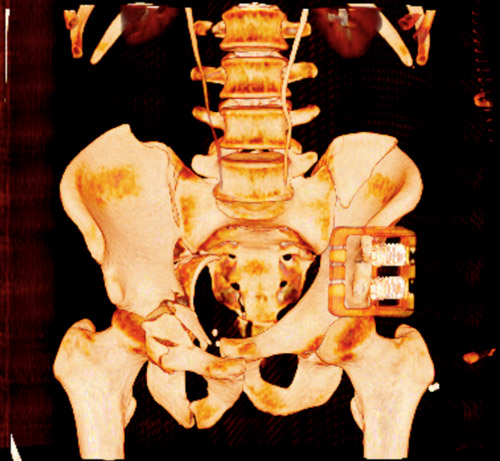

Emergency CT-scan with overthigthened binder

Emergency CT scan